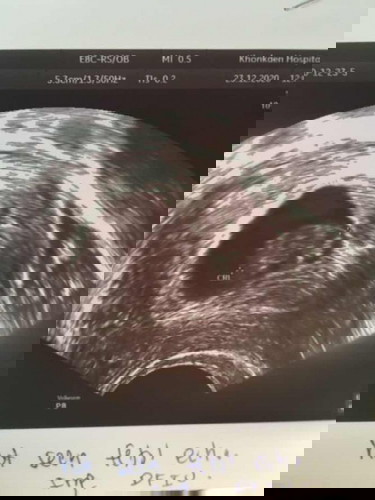

แท้ง3ครั้งเหนื่อยท้อมาก เพราะอยากมีลูกมาก ท้องที่3 เริ่มมีอาการเลือดออกตั้งแต่8วีคออกทุกวัน ตอน8วีคยังเห็นหัวใจเต้นอยู่ พอ 9วีคหมอบอกไม่พบหัวใจน้องเสียชีวิตแล้ว วันนี้ 23/12/63คุณหมอบอกให้นอนโรงพยาบาลเพื่อเหน็บยา แต่เรายังทำใจไม่ได้ หมอเลยนัดอีก1อาทิตย์ ใจก็อยากให้เขาออกมาเอง อาการแพ้คัดเต้านมไม่มีเราพึ่งนึกได้ว่าหายไปหลายวันแล้ว มีคุณแม่ท่านไหน เคยแท้งบ่อยแต่ยังมีลูกได้ปกติบ้างค่ะ ตอนนี้กลัวไปหมด กลัวจะเป็นเหมือนเดิม

กำลังตั้งครรภ์